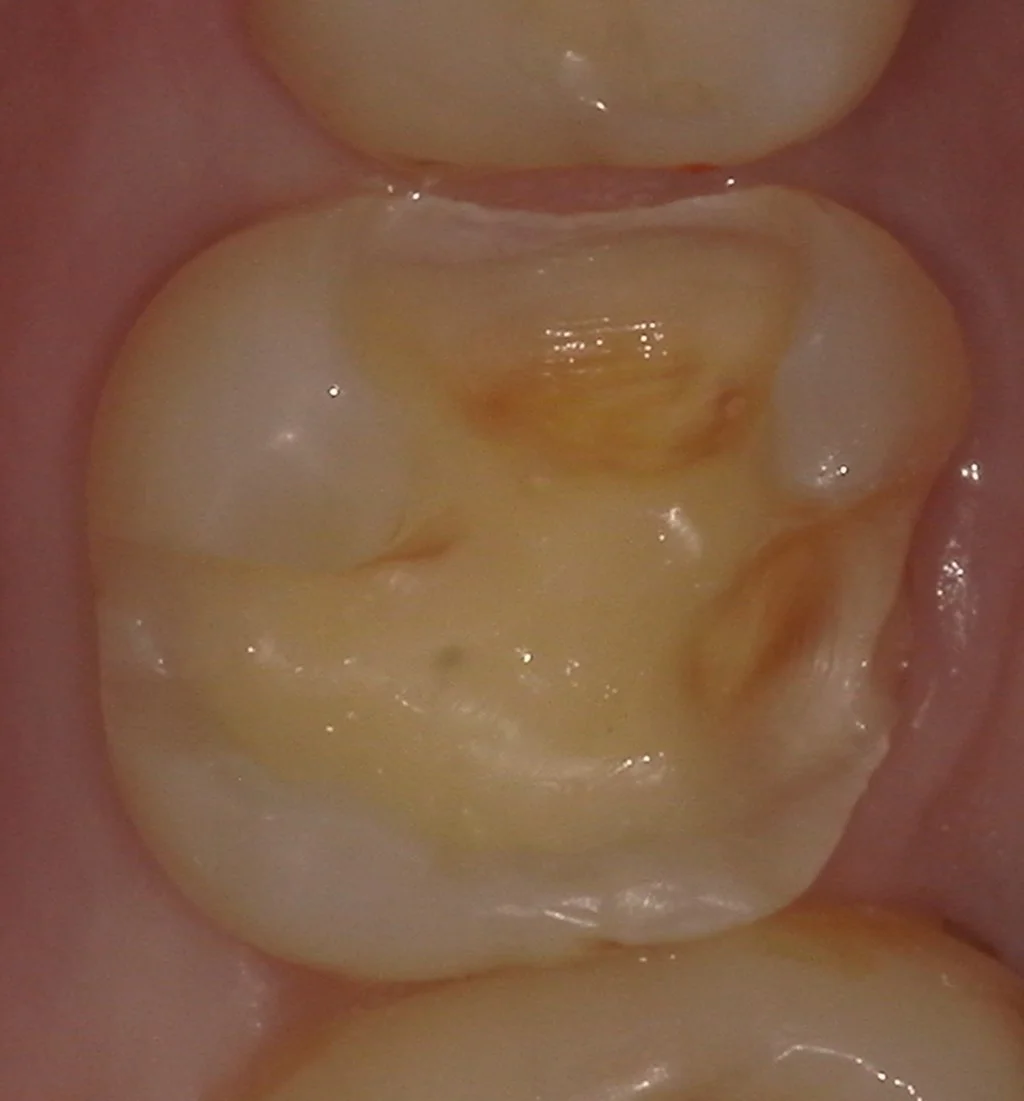

さて、金属を外して虫歯を取ったのがこちらです。

まずは嚙む面からの写真です。

歯の側面も同時に治療したケース。|坂寄歯科医院(取手市藤代) - 画像3

歯の一部に着色が残っているのが分かるかと思いますが、この部位は虫歯が深すぎて、着色部分を除去すると神経が出てしまう危険性があった場所になります。

色自体は残っていますが、虫歯は残っていません。

本来であれば接着の面から言えば全て除去することの方が望ましいですが、そのせいで神経が出てしまうと本末転倒なので、私は深い部分の着色は無理に除去せずに残していることが多いです。

非常に内面の深くにまで虫歯が入り込んでいました。